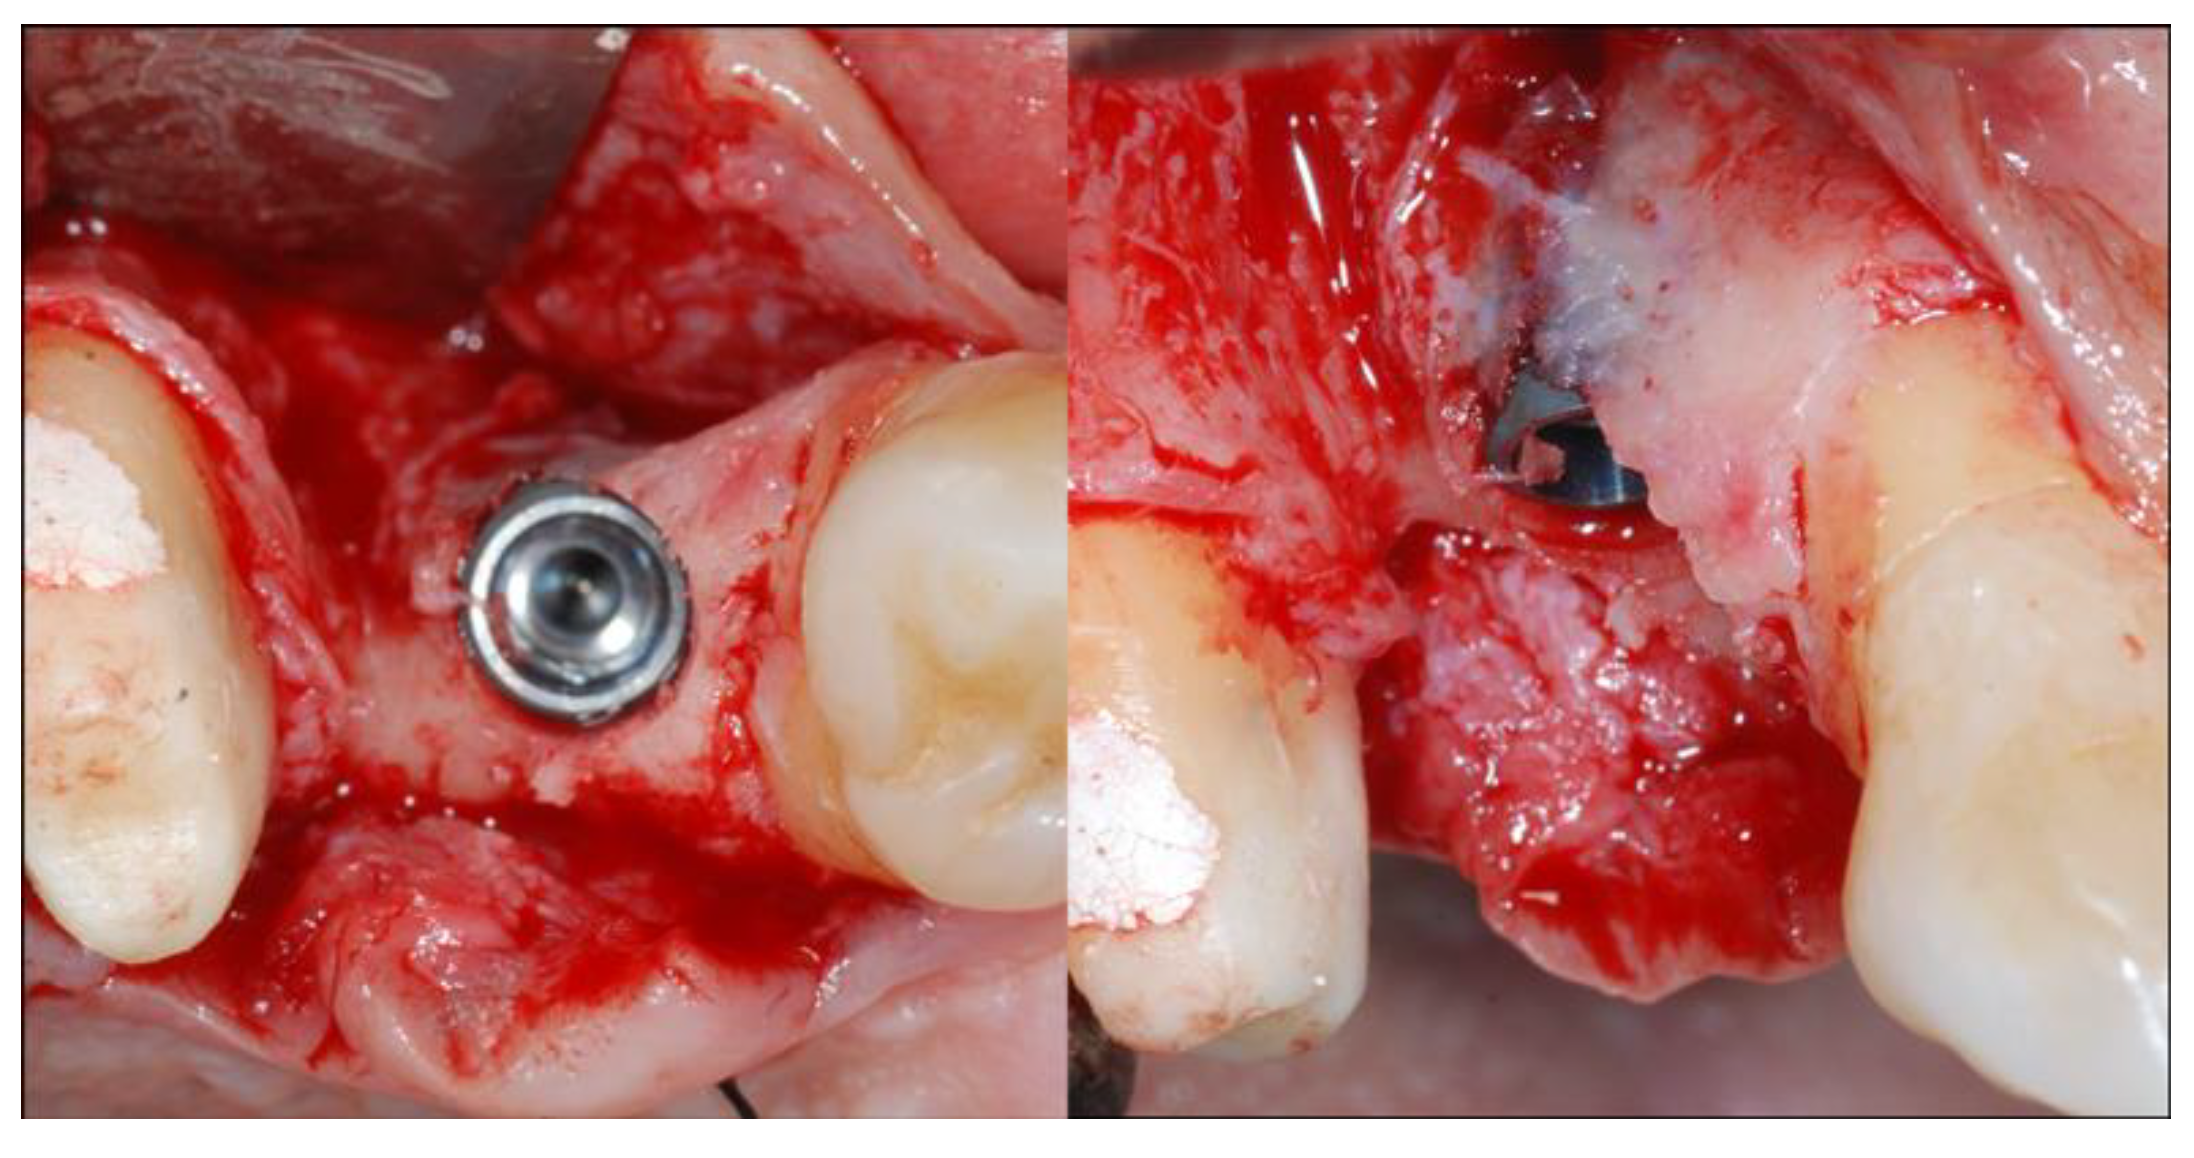

2.4. Surgical Phases